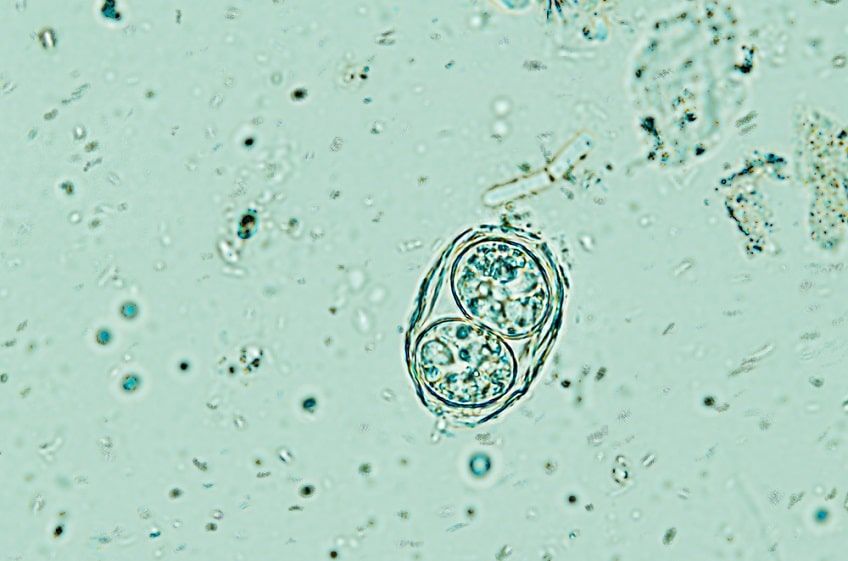

Toksoplazmoza jest chorobą zakaźną, do zakażenia którą dochodzi głównie poprzez połknięcie inwazyjnych oocyst pierwotniaka Toxoplasma gondii. Są one obecne m.in. w surowym mięsie lub środowisku zanieczyszczonym odchodami zakażonego kota. Najczęstszą przyczyną infekcji u ludzi jest spożywanie niedogotowanego mięsa – głównie świń, owiec i kóz. Jednak przeciwciała świadczące o przebytej chorobie wykrywa się również u wegetarian, którzy zarażają się toksoplazmozą poprzez zjedzenie nieumytych warzyw i owoców. Pierwotniak wywołujący toksoplazmozę może przedostać się do organizmu także poprzez łożysko w trakcie ciąży oraz podczas kontaktu z krwią zakażonego osobnika.

Źródłem zakażenia dla kotów wychodzących są przede wszystkim gryzonie i ptaki, które padają ofiarą polowania. W przypadku kotów niewychodzących przenoszenie się choroby związane jest głównie ze spożywaniem surowego mięsa i korzystaniem z kuwety, do której dostęp ma inny kot wydalający oocysty wraz z kałem. Koty chorują na toksoplazmozę tylko raz i rozprzestrzeniają pasożyty tylko przez 14 dni. Jednak podczas choroby mogą wydalić nawet miliony oocyst, które odporne są na warunki środowiska i środki chemiczne, a w zakażonej wodzie mogą przetrwać nawet kilka lat. Oocysty stają się inwazyjne po 1-5 dniach od wydalenia.